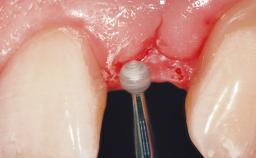

Late Placement of an Implant in a Maxillary Left Central Incisor Site

Soft Tissue Grafting Simultaneous

Soft Tissue Anatomy Intact Defective

Soft Tissue Contour and Volume Slightly compromised